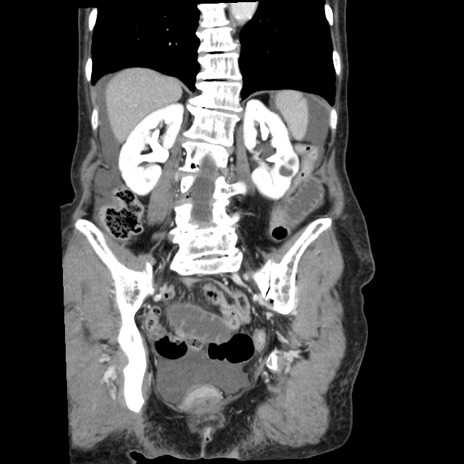

症例1(冠状断像)

症例

【症例】80歳代女性

【主訴】腹痛

【現病歴】8時間前から腹痛あり来院。

【既往歴】糖尿病、脂質異常症、子宮体癌にて子宮全摘術

【身体所見】意識清明・会話良好だが腹痛で苦悶様、全腹部にわたって反跳痛と圧痛あり

【データ】WBC 13600、CRP 0.14、LDH 224、CK 90